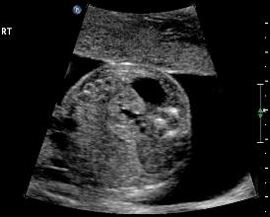

Large Definitive Adrenal Mass

Above. Longitudinal view. Large 3.4 X 2.8 cm mass, hyperechoic structure with small cystic-like clusters. Possibilities include neuroblastoma.

Above. Transverse view. Same patient as immediately above. Large echogenic adrenal mass, possible neuroblastoma versus sub-diaphragmatic pulmonary sequestration. Feeding vessel was not demonstrated.